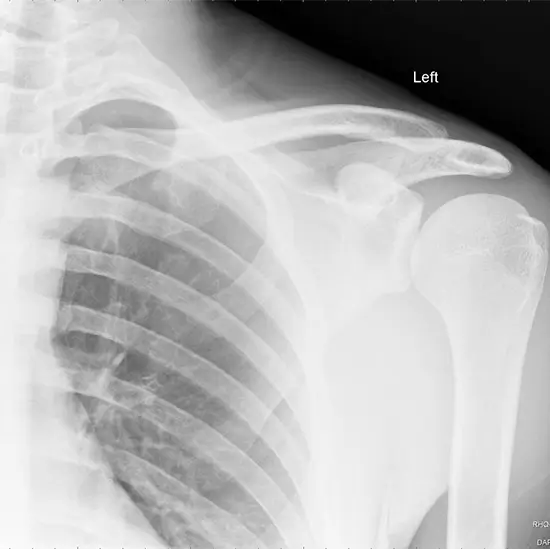

An X-ray of the scapula (shoulder blade) is used to see the shoulder blade and the soft tissues (skin and muscles) around it. The scapula is a bone that looks like a triangle and connects the collarbone to the upper arm bone and the chest wall.

• To diagnose and monitor scapula (shoulder blade) fractures.

• To diagnose infection, deformities, or abnormal bone growth.

• To find out about a winged scapula (a condition in which the shoulder blade protrudes from the back).